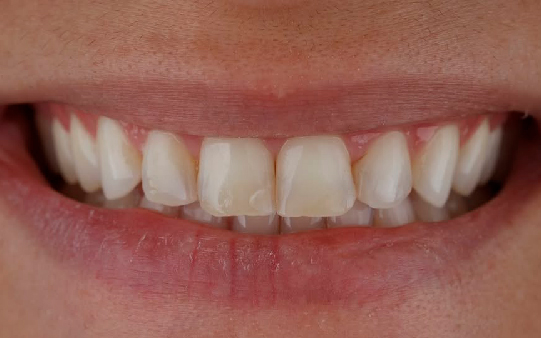

Baixa autoestima e dificuldade para sorrir

Desafios no relacionamento social devido a inseguranças

Desafios psicológicos relacionados à sua saúde bucal